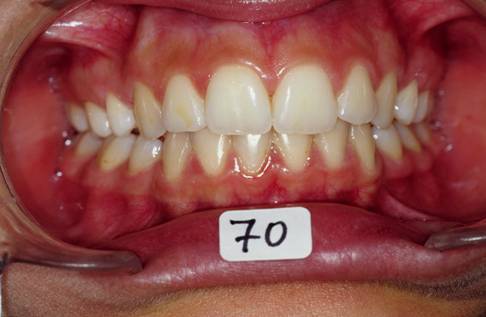

Pour finir j'etaits oblige de changer mon plan de traitement et accepter la solution par extraction de 4X4 et finir en classe I dentaire et legere tendance de classe II squelletique. L'ensemble du cas est tres acceptable, la patiente est tres contente, son sourir pas mal du tout, meme si ce n'est vraiment mon point de vu!!! Mais voila un cas ou j'etaits oblige d'extraire pour des raisons multiples, morphologie ethnique, maturation precoce, demande esthetique de la part de la patiente, des erreurs mecaniques de ma part? peut etre bien mais ca s'est passe comme ca... voici les photos

13 ipxuzs - Eugenol

14 f0gqim - Eugenol

15 myewxj - Eugenol

16 d66e2q - Eugenol

Suite et fin.

Il faut preciser une chose: Suivre un cas sur le forum ce n'est pas pareil comme vivre ce cas pendant le traitement. Le sourir fige sur photoo n'est pas aussi expressif et reel comme en clinic. La pression mise par les parents parfois est tellemnt forte qu'on finit par ceder.

Voila la fin de l'histoire...